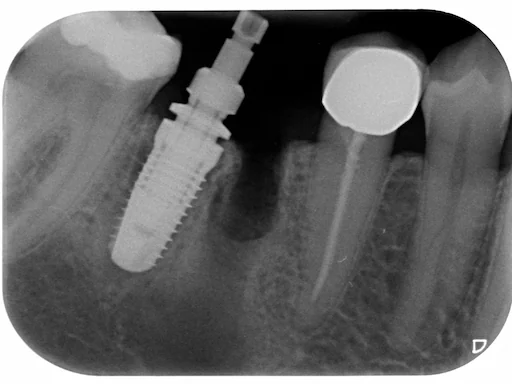

Patientenfall - Implantologie - Zahn 46 - 2

Schritt 2

Um der Patientin eine zu lange Behandlungsdauer zu ersparen, wurde beschlossen, die Zyste zu entfernen und das Implantat direkt einzusetzen. Ein solches Vorgehen ist vor allem unter dem Aspekt der Vermeidung weiterer Operationsnarben sinnvoll. In diesem Fall wurde bereits so viel voroperiert, dass das Gewebe nicht mehr optimal durchblutet wird, da bereits so viel Narbengewebe vorhanden ist.

Patientenfall - Implantologie - Zahn 46 - 3

Schritt 3

Der chirurgische Eingriff wurde hier in Narkose durchgeführt und dauerte etwa eine Stunde. Dabei wurde auch Knochen aus dem retropolaren Bereich entnommen, um den großen Defekt mit biologischem Material in Verbindung mit dem LPRF-Verfahren zu versorgen. Dies gewährleistet eine maximale Biologisierung des verwendeten Knochenersatzmaterials.